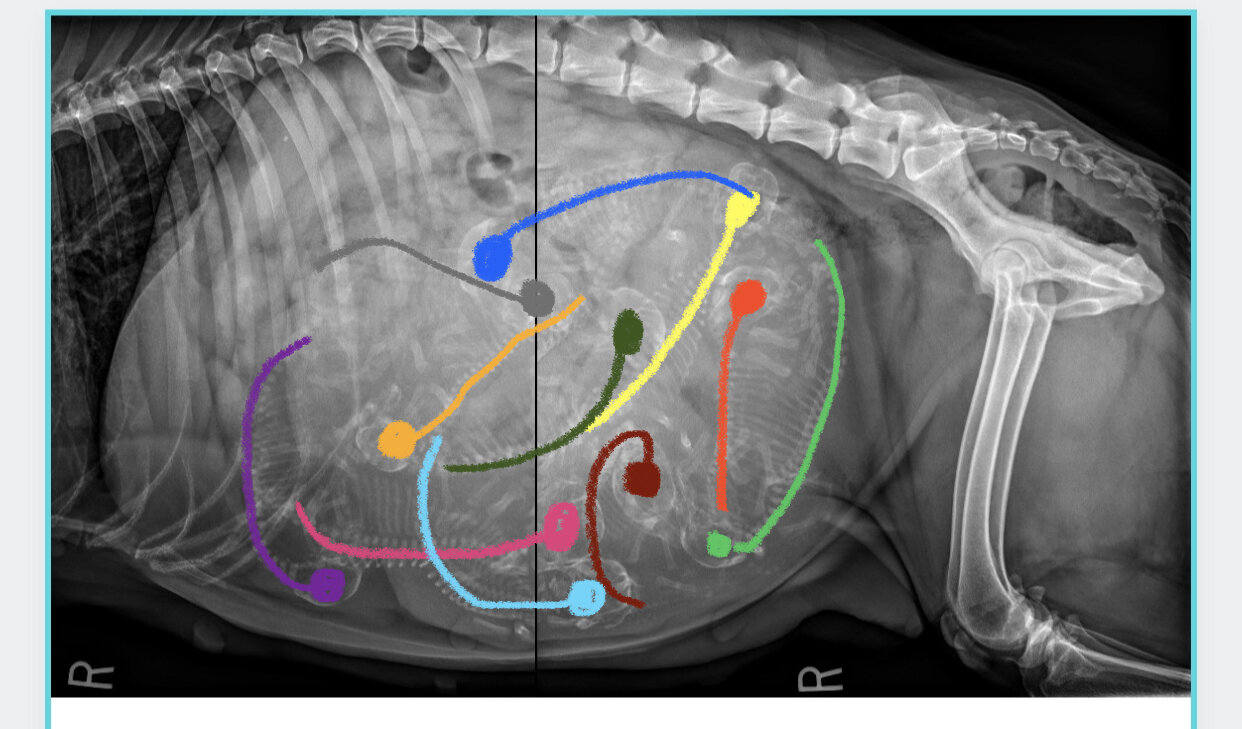

Diagram of puppies in the womb

Diagram of puppies in the womb. Different Positions of Baby in the Womb Knowing what position your baby is in the womb can help you understand how best you can prepare for delivery and what care should be taken during labour or birth. You may have seen your own baby inside your womb during a sonography and wondered about the position of the baby during delivery. Have You Ever Seen Puppies In The Womb? - Puppy In Training Have you ever wondered what puppies look like in the womb? Or what differences there are between breeds or even a Wolf. In The Womb: Dogs chronicles the embryonic journey of wolves and three different dog breeds - The giant Mastiff, the agile medium sized Golden Retriever, and the smallest of... At What Age Do Puppies Calm Down? | Avid Pup Puppies are big balls of energy! Whether they're following your every move around the house or they're off in the corner getting into some trouble, your Truth is, puppies don't mature and calm down at a set age. All dogs are different. Some puppies even come out of the womb with a seemingly mellow... I need a chart on the growth of puppies in the womb. I would My yorkie puppy was the only puppy that the Female Yorki had just 1 puppy and the puppy is off the charts in her weight for her age she is 1 A CHART ESTIMATING THE GROWTH OF PUPPIES INSIDE THE WOMB.A CHART FROM CONCEPTION TILL RIGHT BEFORE DUE DATE… read more.

Stages of Dog Pregnancies & Puppy Development - Daily Puppy Where pups are positioned in their mother's womb can affect their development and behavior later in life. Pups' neighbors in the womb can have an interesting effect later on in life. While in the womb, boy pups secrete the male hormone testosterone as their testes develop.